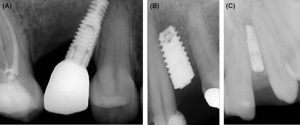

ایمپلنت های دندانی به دلیل ساختار منحصر به فرد خود، از سایر ترمیم های دندانی متمایز هستند. آنها از یک پایه تیتانیومی و تاج مصنوعی تشکیل شده اند که به طور کامل جایگزین کل ساختار دندان از دست رفته می شود. بر خلاف پروتزها و بریج هایی که تنها جایگزین قسمت قابل مشاهده دندان ها می شوند و روی لثه قرار می گیرند، ایمپلنت ها جایگزین ریشه و تاج دندان ها می شوند.

پایه تیتانیومی ایمپلنت دندانی با جراحی مستقیماً درون استخوان فک قرار داده می شود. با گذشت زمان، پست محکم می شود زیرا استخوان اطراف از طریق استئواینتگریشن با آن یکپارچه می شود. این استئواینتگریشن، ریشه طبیعی دندان را تقلید می کند و این امکان را برای ایمپلنت های دندانی فراهم می کند تا زمانی که استخوان فک آن را تثبیت کرد، به طور مستقل بایستد. بنابراین، ایمپلنت های دندانی به حمایت از دندان های اطراف متکی نیستند و راه حلی مستقل برای ترمیم دندان ها ارائه می دهند.

اگر مقدار قابل توجهی از تراکم استخوان قبلاً در فک و دندان از بین رفته باشد، برخی از بیماران ممکن است فکر کنند ایمپلنت دندانی دوام ندارد. اما لزوماً اینطور نیست. پیوند استخوان می تواند بافت استخوانی را به محل تخلیه شده اضافه کند و امکان قرار دادن موفق ایمپلنت دندانی را فراهم کند.

روش پیوند استخوان شامل برداشتن بافت استخوانی از محل اهداء کننده و قرار دادن آن در ناحیه مورد نظر است. استخوان اهداء کننده می تواند از فک، چانه یا لگن قوی تر باشد. پس از ایمن شدن پیوند، ایمپلنت دندانی را می توان قرار داد و سلامت و عملکرد دهان را احیاء کرد.